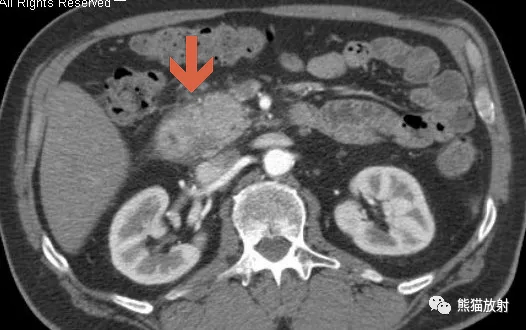

男 , 64岁 , 沟槽区慢性胰腺炎(单纯型) 。

a)CT平扫示胰头与十二指肠降部的间隙内有软组织密度灶(箭) , 边界欠清 , 周围脂肪间隙模糊、渗出;b)增强扫描动脉期显示沟槽区病灶内有囊变区 , 周围实性病灶呈不均匀强化;c)增强扫描实质期 , 显示沟槽区病灶呈渐进性延迟强化 , 中心相对低密度区缩小 。 胰头实质呈均匀强化(箭) , 边缘清;d)增强实质期冠状面重组图像 , 显示十二指肠降部副胰管区肠壁不均匀增厚(白箭) , 其内可见低密度囊变区 , 十二指肠降部呈偏心性狭窄 , 胰周多发肿大淋巴结(黑箭) 。